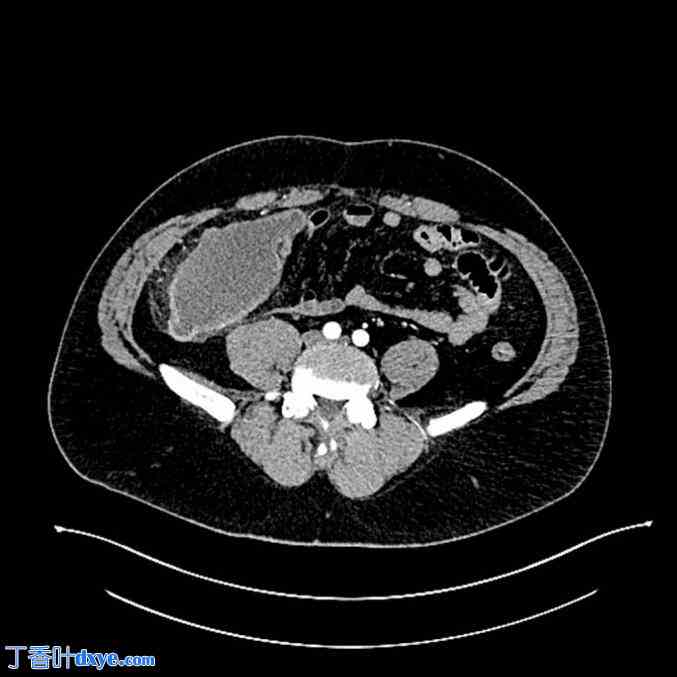

图 2。

腹部CT扫描显示阑尾增大,直径13×7厘米。

,一名 34 岁男性,无重大病史,因右髂窝疼痛到急诊室就诊,提示急性阑尾炎。腹痛不典型,位于中腹部,疼痛轻微,开始后 12 小时,然后定位到腹部右下象限 (RLQ),在入急诊室前 4 天开始。还伴有恶心、食欲减退和便秘。无腹泻或发烧,未使用止痛药。无相关手术、家族、药物、过敏、医疗或心理社会史。血液检查显示 D-二聚体水平升高 (647 ng/ml),无白细胞增多症,无中性粒细胞增多症。体格检查显示右下象限中度肌性阻力,McBurney 和 Blumberg 征阳性。腹部超声检查显示盲肠处有一个低回声二尖瓣环肿块,最大直径为 85 mm,结肠周围有积液(阑尾回盲部扩张,管腔低回声,壁层增厚,周围脂肪弥漫性高反射)(图 1)。随后,进行腹部 CT 扫描,显示阑尾肿块具有粘液囊肿的特征(图 2),阑尾严重液性扩张,直径为 13 × 7 cm。随后进行腹腔镜探查(图 3),发现阑尾内有肿瘤性肿块。由于粘连并为了避免肿块破裂,进行了开腹手术。最后,阑尾成功切除,术中无破裂,术后恢复顺利,患者于两天后出院。组织学检查(图 4)显示阑尾高级别粘液肿瘤局限于粘膜下层(pT3),伴有急性蜂窝织性阑尾炎。患者被送往专科腹膜切除术科,两个月后接受右回盲部切除术和预防性 HIPEC。决定进行预防性 HIPEC 是因为患者年龄较小,手术风险相对较低,且浆膜下层存在粘液湖。第二次手术的组织学检查未显示局部或播散性肿瘤的迹象。